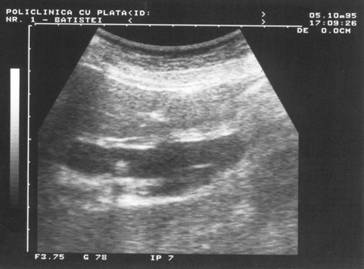

mediul strabatut (lichidian) si cel ce urmeaza (solid).

Figura 16. Intarire acustica posterioara la nivelul vezicii urinare.

Figura 17.}ntarire acustica posterioara la nivelul V.B.